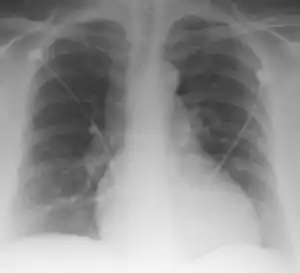

Palla's sign is a clinical sign in which an enlarged right descending pulmonary artery is seen on the chest x-ray in patients with pulmonary embolism. It is of low sensitivity, and its specificity is not known. It exhibits as a "sausage" appearance on X-ray. [1]

| Palla Sign and Westermark Sign | |